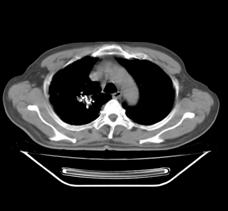

典型病例1:患者鞠xx,女,68岁,住院号:488141,因左胸痛1月余入院。2015年3月31日胸部增强CT示:左肺下叶2.5cmx2.8cm占位,左侧第三前肋骨溶骨性转移、形成厚约3cm肿块,左侧腋窝淋巴结2.1cmx4.1cm及前纵膈淋巴结转移。患者于2015年4月1日经CT引导下穿刺活检、病理证实为左肺下叶腺癌。于2015年4月5日对其采用125I放射性粒子置入治疗。治疗3个月随访,患者胸痛缓解,左肺下叶原发病灶消失,粒子聚集;左侧第三前肋骨基本恢复正常形态;前纵膈淋巴结消失,粒子聚集;左侧腋窝淋巴结缩小2/3。目前患者生活质量良好,可从事一般家务劳动。

术前CT片:

术后三个月CT片: